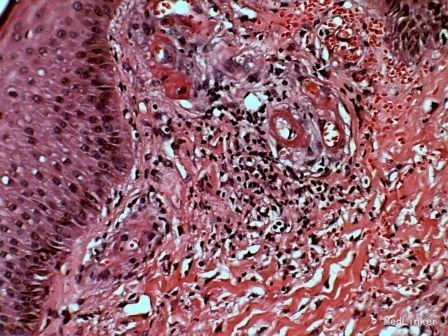

查体:双下肢多发淡红褐色可触性紫癜,踝部溃疡。 辅助检查:ANA 1:320, 颗粒型,pANCA阳性 补体C3下降 病理:血管周围为中性白细胞浸润,有核尘。伴有红细胞渗出,炎性细胞浸润在真皮上部,血管壁也有中性白细胞侵犯,血管有的模糊不清及坏死,血管周围及血管壁有纤维蛋白束的沉积,溃疡是由于血管坏死引起,同时可见含铁血黄素的沉积。

诊断:变应性血管炎 治疗:强的松,消炎痛